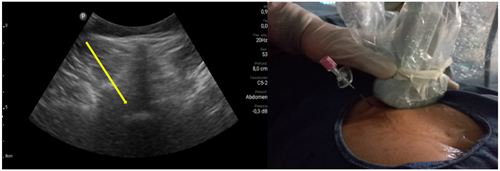

Pacientes y métodos: Un total de 25 pacientes con dolor radicular lumbosacro fueron seleccionados para recibir inyecciones epidurales interlaminares de esteroides en posición decúbito dorsal, utilizando la técnica ecoguiada en plano, en tiempo real, en eje corto o transversal. En todos los casos, un epidurograma de control fue realizado previo a la inyección de la solución de esteroides. El rendimiento de la técnica fue estudiado mediante la tasa de éxito de la misma, entendido como éxito a la obtención de un epidurograma sin necesidad de abandonar la técnica ecográfica en un tiempo menor a 10 minutos. El rendimiento del procedimiento fue estadísticamente evaluado por el método de la suma acumulativa (CUSUM), y la curva de aprendizaje aplicando este método fue construida.

Resultados: La distancia promedio desde la piel al complejo posterior evaluada por el escaneo ecográfico previo al procedimiento fue de 6,7 ± 1,8 cm. De los 25 procedimientos realizados, en 21 se alcanzó el espacio epidural sin ayuda de la fluoroscopia, en un tiempo promedio de 4,8 ± 1,2 minutos. Esto constituye una tasa de éxito del 84 %. En los cuatro procedimientos restantes el espacio epidural fue alcanzado con éxito mediante el uso complementario de la fluoroscopia.

Figura 1